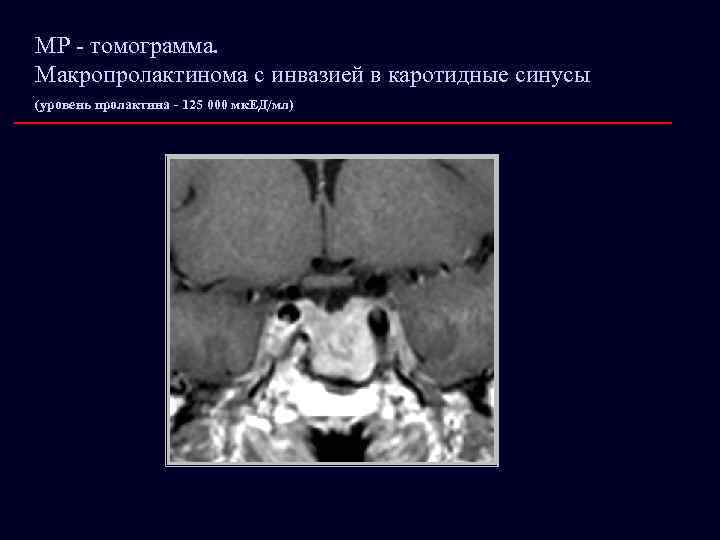

МР - томограмма. Макропролактинома с инвазией в каротидные синусы (уровень пролактина - 125 000 мк. ЕД/мл)